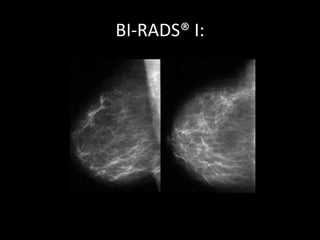

• Categoria I não há alteração detectável ao

exame.

• Sugere-se controle anual.

BI-RADS® I: